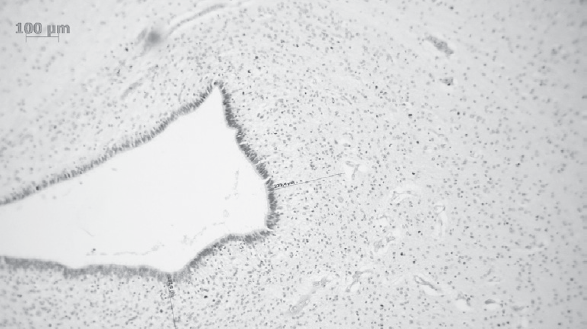

Результаты патоморфологического исследования ткани головного мозга в области герминального матрикса боковых желудочков. Толщину герминального матрикса измеряли в передних отделах боковых желудочков мозга. Толщина герминального матрикса изменялась обратно пропорционально ПКВ умерших детей (табл. 3, рис. 8, 9). Необходимо подчеркнуть, что у двоих умерших недоношенных новорожденных, ПКВ которых достиг 36 недель, при микроскопическом исследовании материала передних отделов боковых желудочков герминальный матрикс сохранялся.

Рис. 8. Тонкий слой герминального матрикса у ребенка, ПКВ 37–38 недель (окраска гематоксилином и эозином, ×100)

Fig. 8. A thin layer of the germinal matrix in a child, PCA 37-38 weeks (hematoxylin-eosin stain, ×100)

Рис. 9. Широкий слой герминального матрикса у ребенка, ПКВ 31–32 недели (окраска гематоксилином и эозином, ×100)

Fig. 9. A wide layer of the germinal matrix in a child, PCA 31-32 weeks (hematoxylin-eosin stain, ×100)